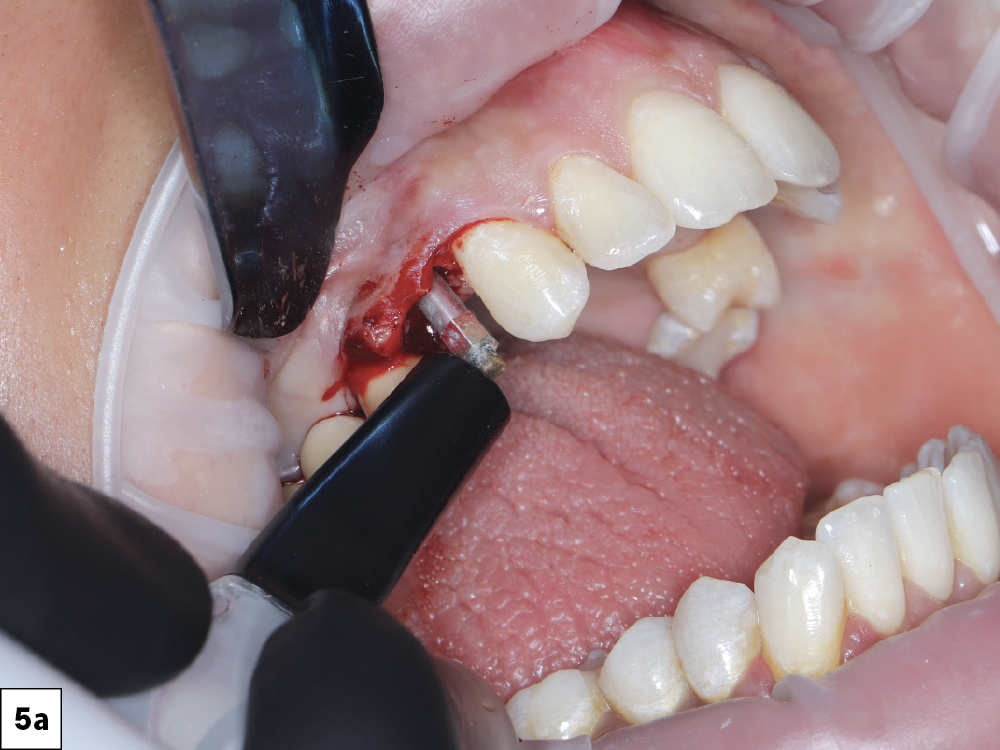

Figures 5a–5c: Resonance Frequency Analysis (RFA) was used to confirm an Implant Stability Quotient (ISQ) appropriate for immediate loading.